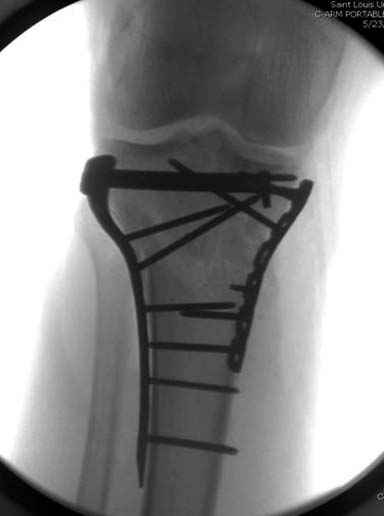

Решили выполнить остеосинтез штифтом и внутрисуставного перелома пластиной и винтами. Жду мнения! Зачем мне оправдываться-я же не преступник. Диалогом называется...

При переломах одного из мыщелков тибиал плато+дополнительный перелом проксимальной трети большеберцовой кости можно применить комбинированный вариант фиксации, т.е. мыщелок винтами или пластиной, а для диафиза можно установить гвоздь. В данном варианте потеряно преимущество гвоздя , из-за серьезной травмы суставной поверхности нельзя нагружать ногу несколько месяцев. А без нагрузки гвоздь просто заполнитель пространства внутри кости!

На вашем место я бы подождал с фиксацией до готовности кожных покровов, и за это время можно было подобрать соответствующий фиксатор, т.е более длинная пластина снаружи и медиальная пластина на апексе перелома как подпорка. Здесь приемлем как раз минимальный доступ.

Здесь пару случаев для сравнения,...в первых 1-4 слайдах метод фиксации одним фиксатором, как видно после 8 месяцев сохранилась ось. С 5 по 9 вариант двумя пластинами...